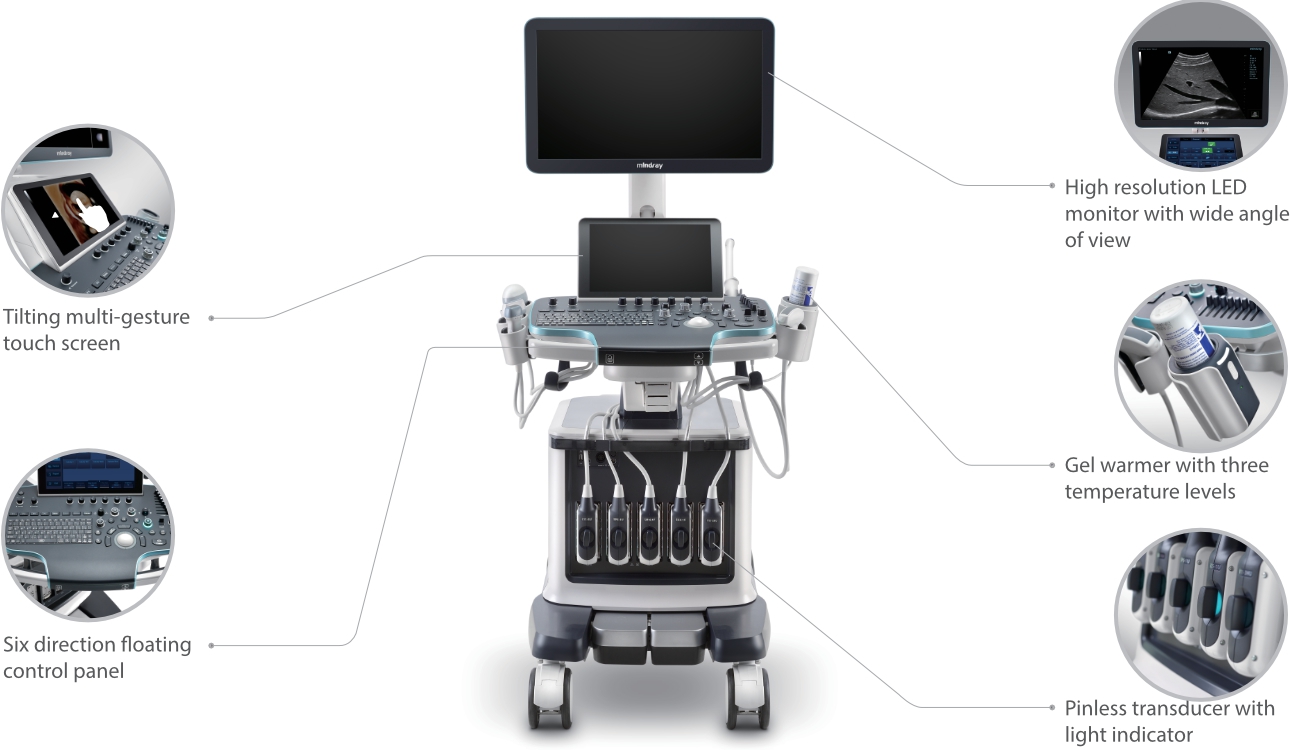

Desde que se fund├│ la compa?├Ła, Mindray ha explorado incansablemente nuevas formas de mejorar la confiabilidad del diagn├│stico. Con la revolucionaria tecnolog├Ła de ZONE Sonography?, la nueva plataforma ZST+ de Resona?7 lleva la calidad de la imagen por ecograf├Ła a un nivel superior mediante el procesamiento de datos de canal y la adquisici├│n de zona.

Adem├Īs de la calidad de imagen de primer nivel, Resona?7 tambi├®n mejora las capacidades de investigaci├│n cl├Łnica con el revolucionario V?Flow para la evaluaci├│n hemodin├Īmica vascular y con la adquisici├│n de planos m├Īs inteligente a partir de conjuntos de datos 3D para el diagn├│stico del SNC fetal. Al combinar el funcionamiento multit├Īctil basado en gestos m├Īs intuitivo y todas las caracter├Łsticas cl├Łnicas esenciales, Resona?7 realmente lidera las novedades en innovaci├│n de ecograf├Łas.